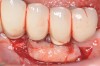

Fig 2. Radiograph suggested moderate bone loss around the implants.

Figure 2

Dental implants have revolutionized the way in which clinicians treat and restore partially and fully edentulous patients and have demonstrated success for managing a broad range of clinical dilemmas. While implants have been highly predictable and have achieved long-term success, they are not immune from complications associated with improper treatment planning, poor surgical and prosthetic execution, material failure, and inadequate or infrequent maintenance. Among these problems are the biologic complications of peri-implant mucositis and peri-implantitis, which are inflammatory conditions in the soft and/or hard tissues surrounding dental implants (Figure 1 through Figure 4).1,2